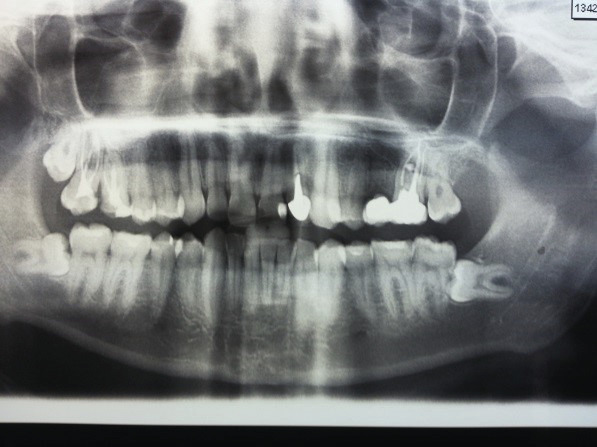

Un panoramique dentaire récent ne montre pas d’image claire au niveau de la racine de la dent n° 16 (photo 2 ) mais un petit débord de pâte d’obturation canalaire. Un cliché rétro-alvéolaire ciblé sur les dents n° 16 et 17 est réalisé. Il pose le diagnostic de fistule vestibulaire bourgeonnante due à une lésion périradiculaire vestibulaire de la dent n° 16, après traitement endodontique.